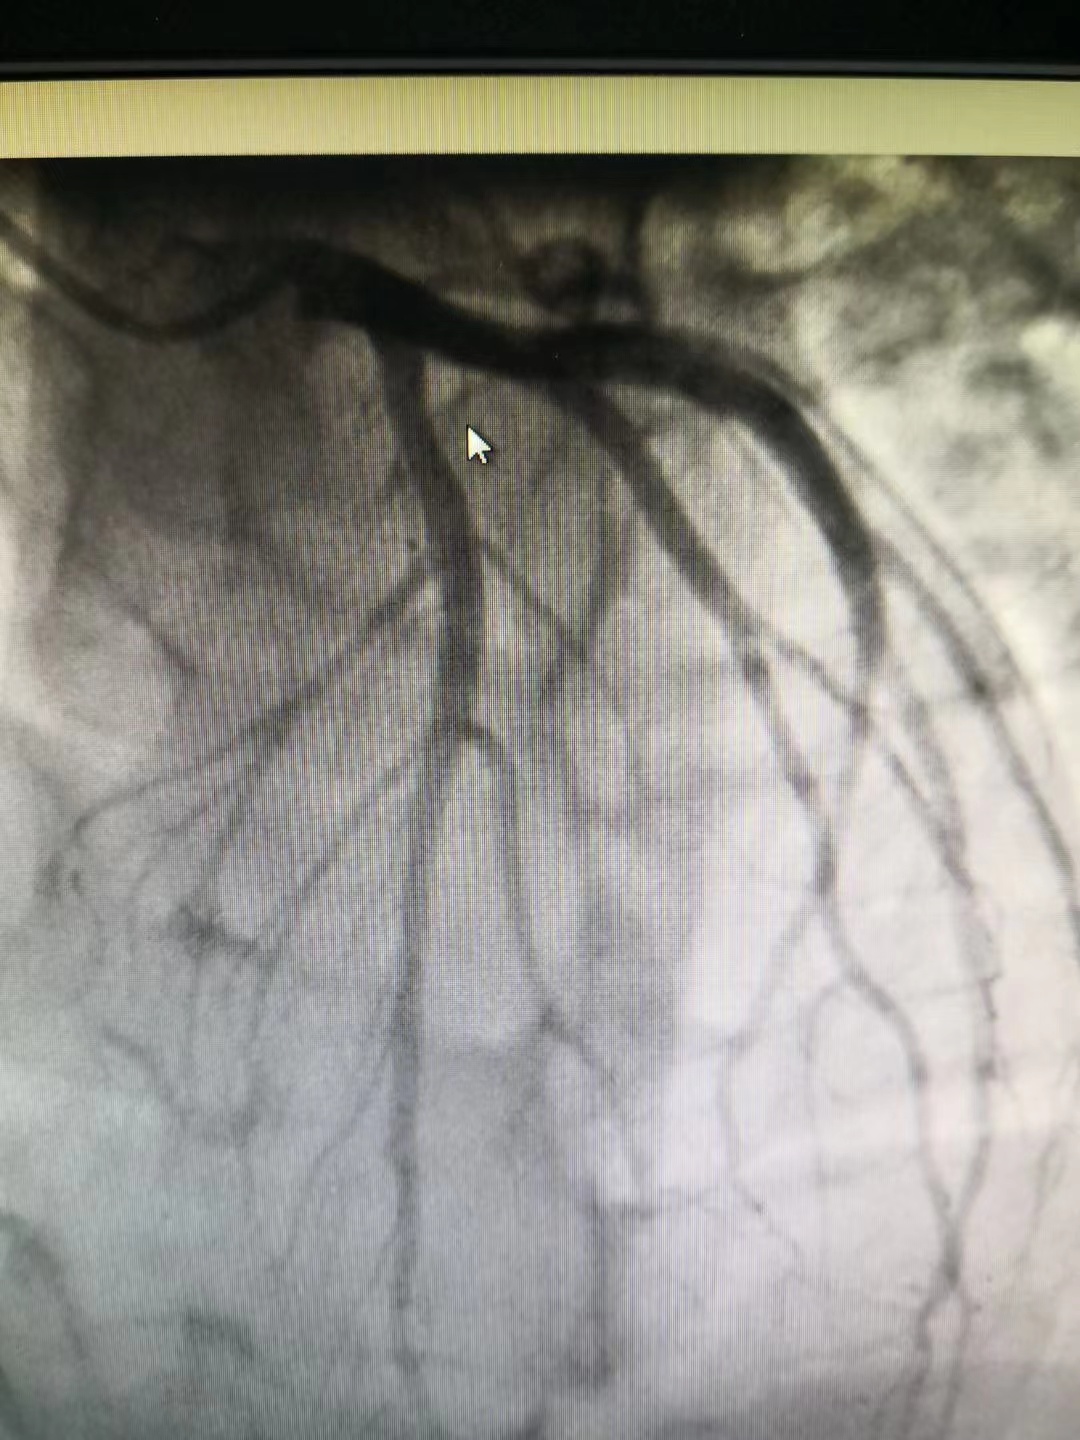

冠脈造影提示前降支近段50%局限性狹窄,遠(yuǎn)端肌橋

小貼士:冠狀動(dòng)脈造影(CAG)

冠狀動(dòng)脈造影(CAG)是一項(xiàng)用于檢查動(dòng)脈血管是否正常的輔助檢查,是診斷冠心病的有效方法之一。將導(dǎo)管經(jīng)大腿股動(dòng)脈或其它周圍動(dòng)脈插入送至升主動(dòng)脈,再插入左或右冠狀動(dòng)脈口,注入造影劑,使冠狀動(dòng)脈顯影。CAG能較明確地揭示冠狀動(dòng)脈的解剖畸形及其阻塞性病變的位置、程度與范圍,是目前唯一能直接觀察冠狀動(dòng)脈形態(tài)的論斷方法,醫(yī)學(xué)界稱其為“金標(biāo)準(zhǔn)”。